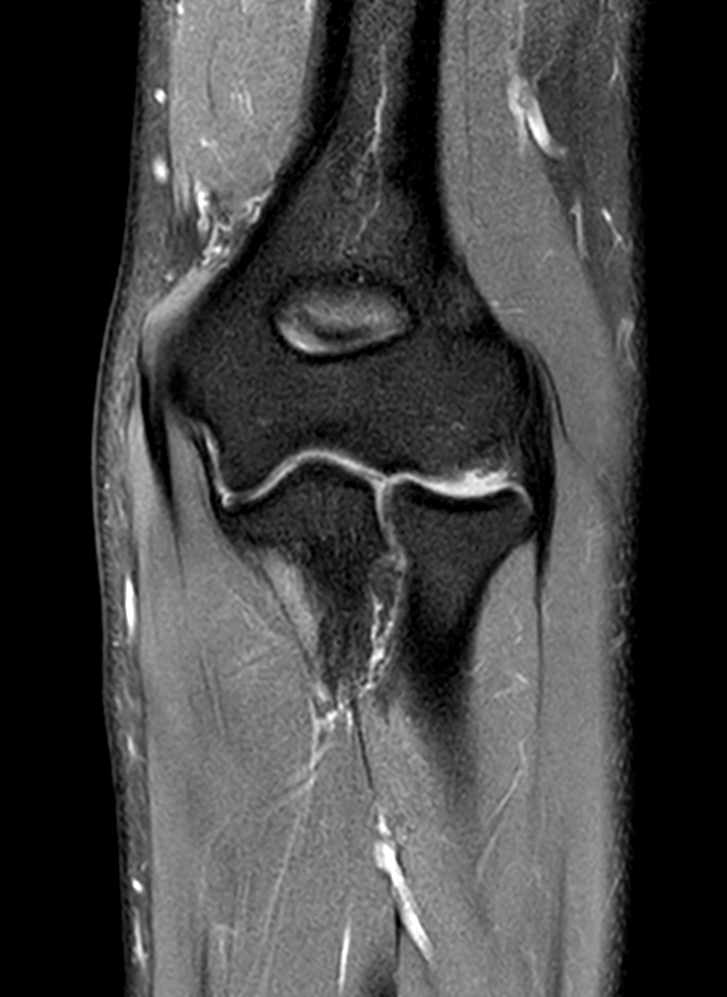

High quality Elbow imaging with Compressed SENSE

Spital Uster, Switzerland